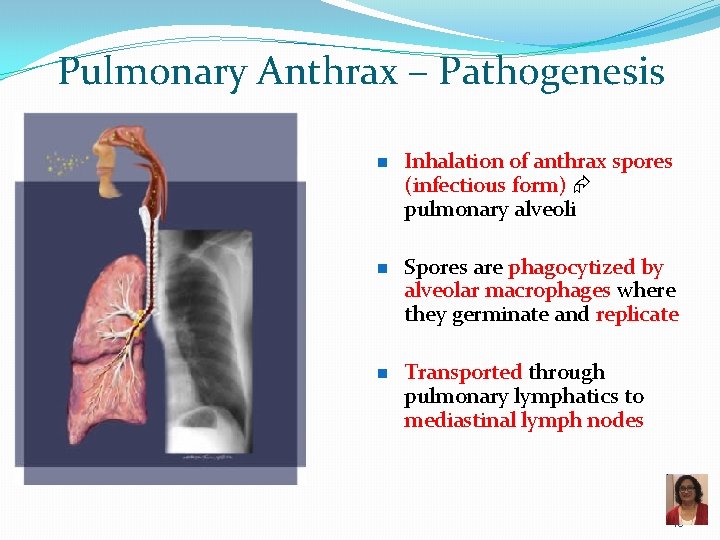

Pulmonary Anthrax – Pathogenesis n n n Inhalation of anthrax spores (infectious form) pulmonary alveoli Spores are phagocytized by alveolar macrophages where they germinate and replicate Transported through pulmonary lymphatics to mediastinal lymph nodes 46

Pulmonary Anthrax – Pathogenesis n Exotoxins production hemorrhage and edema in the lymph nodes and mediastinum: mediastinal hemorrhagic lymphadenitis q n n Mediastinal widening Pleural effusions and thickening of the bronchovascular bundles Ultimately, bacteria enter blood stream severe septicemia, meningitis and often death 47